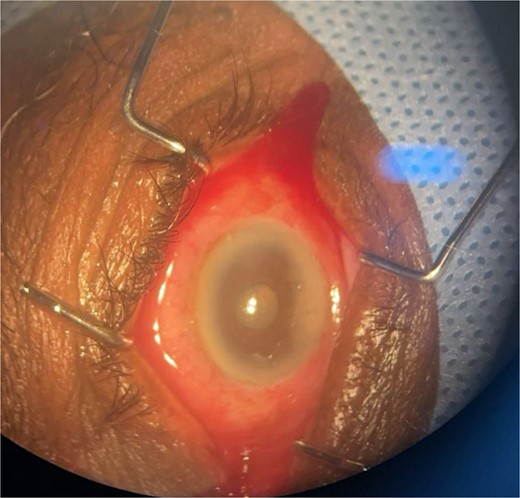

Patient 2: A 69-year-old Saudi female experienced severe right eye pain after surgery on the same day as patient 1. Visual acuity was reduced to hand motions, and examination showed conjunctival ciliary injection, corneal edema, and hypopyon (Fig. 3). B-scan confirmed vitritis (Fig. 4). She received similar emergency interventions as patient 1.

B-scan ultrasound showing moderate vitreous echoes and vitreous abscess in patient 2.